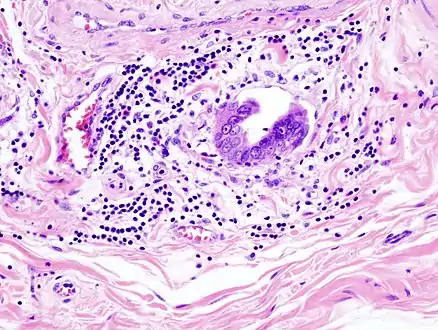

Xanthogranulomatous cholecystitis (XGC) is a rare form of gallbladder disease which mimics gallbladder cancer although it is not cancerous.[16][17] It was first discovered and reported in the medical literature in 1976 by J.J. McCoy Jr., and colleagues.[16][18]